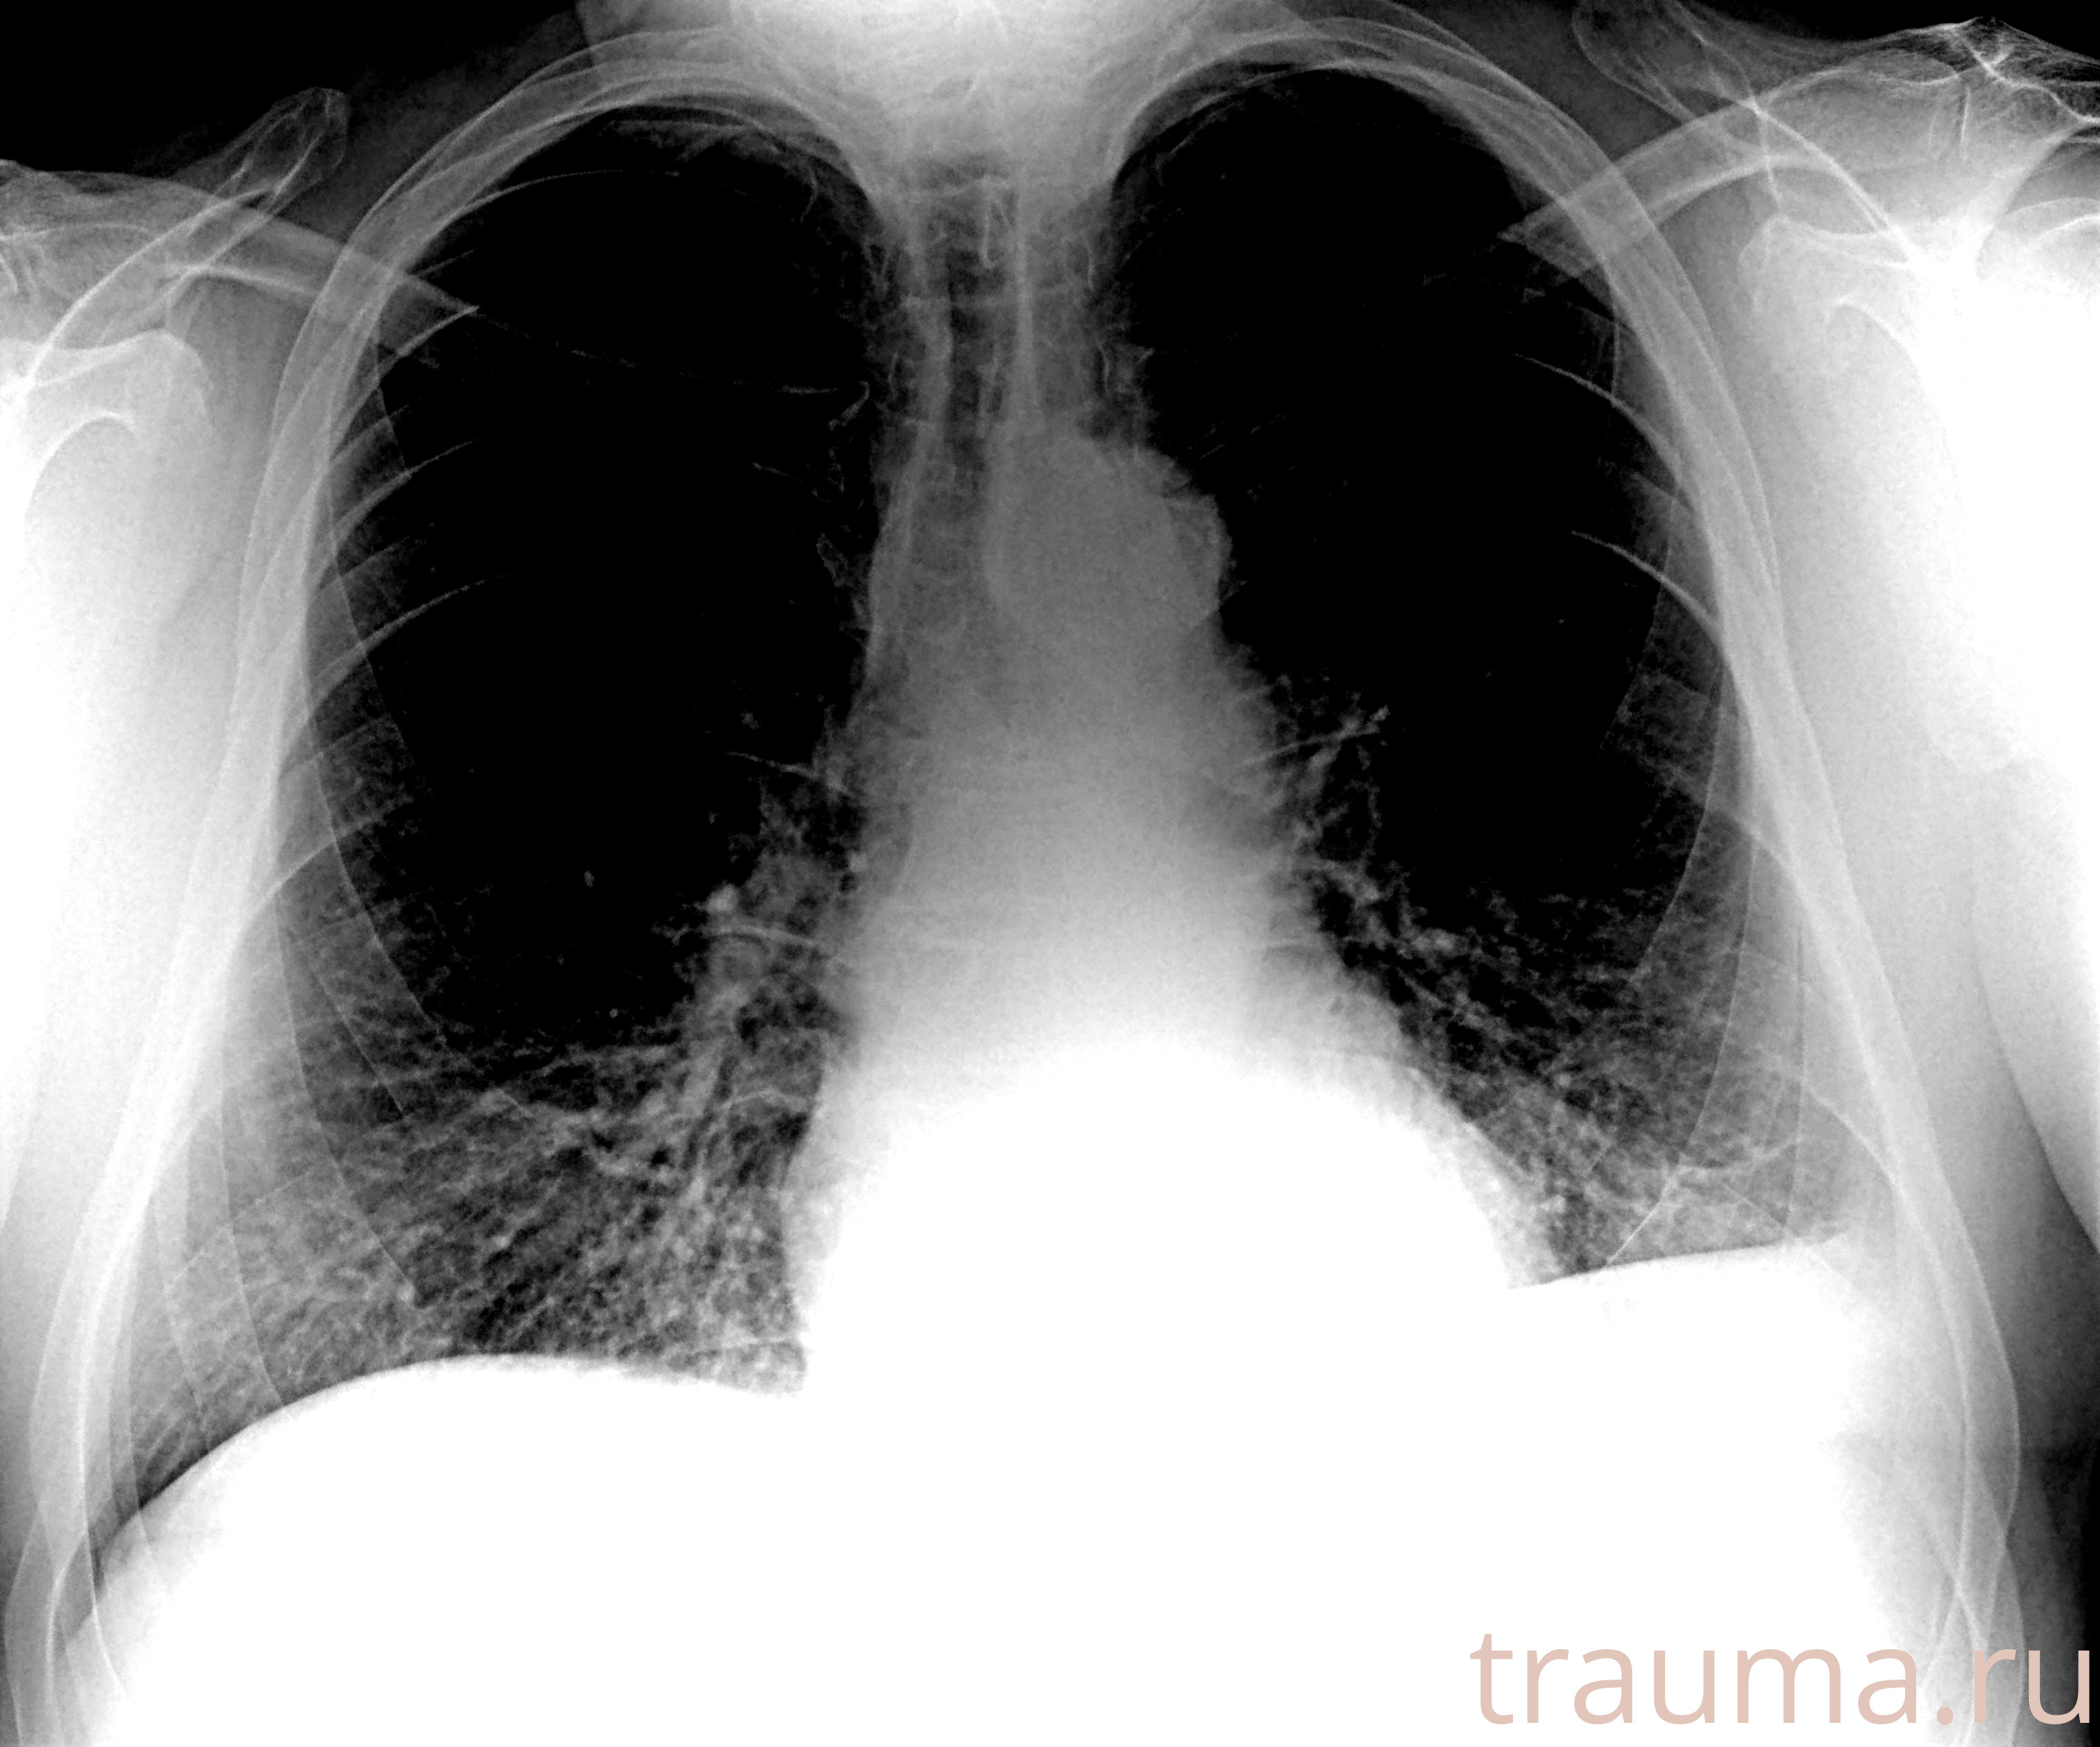

Рентгенограммы

Рентген на дому: по вашему адресу приезжает врач-рентгенолог, травматолог-ортопед с мобильным рентгеновским аппаратом, проводит диагностику травмы или заболевания, делает необходимые рентгенограммы, дает рекомендации по дальнейшему лечению. Получить качественные снимки в домашних условиях возможно благодаря уникальной методике, разработанной МосРентген Центром для института  Склифосовского

при переломе шейки бедра и пневмонии от компании МосРентген Центр - партнера Института имени Склифосовского